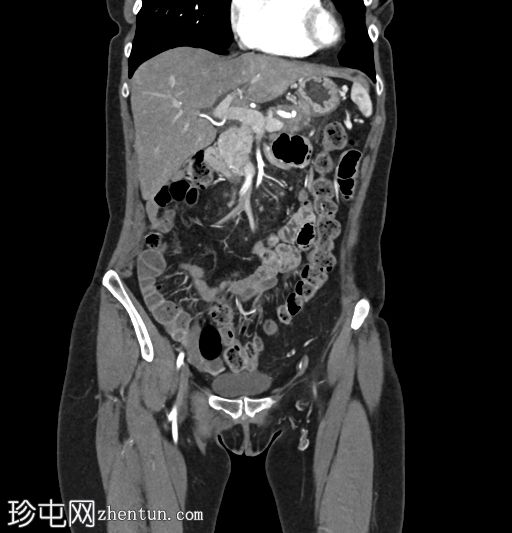

冠状位增强扫描

动脉期

术后改变符合慢性胰腺炎Beger手术的影像学表现。胰头显影良好,结构完整;胰尾可见主胰管扩张,系远端胰肠吻合口处浸润性肿块所致。该肿块浸润脾动脉和脾静脉,并伴有血管周围侵犯,以及胰周脂肪浸润。此外,肠系膜可见线状软组织密度影,提示腹膜播散。

左肝叶偶见海狸尾状解剖变异。